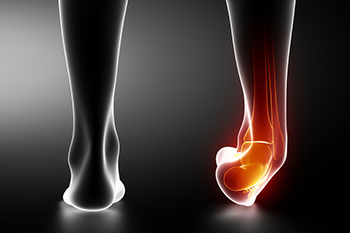

Why Visiting a Podiatrist for an Ankle Sprain Is Important

When the ligaments that hold the ankle in place and connect the bones together become overstretched or torn, an [ankle…